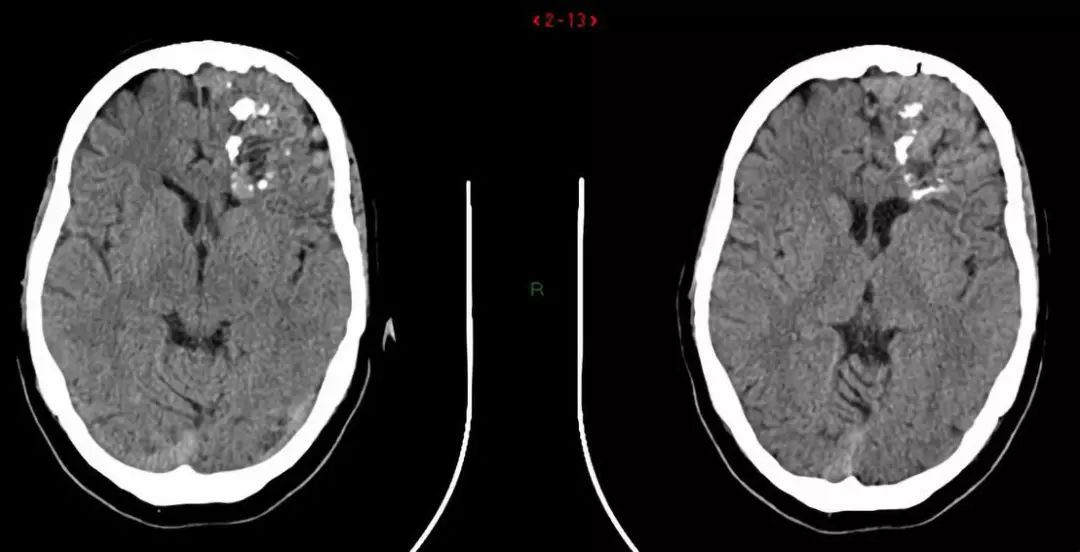

1.成年发病的白质脑病合并轴索球样变和颗粒样胶质细胞(adult-onset leukoencephalopathy with axonalspheroids and pigmented glia,ALSP)

包括临床表型和病理特点十分相似的2种疾病:遗传性弥漫性白质脑病合并轴索球样变(hereditary diffuse leukoencephalopathy with spheroids,HDLS)和家族性颗粒样细胞白质脑病(pigmentary leukodystrophy,POLD)。临床症状包括性格行为改变、精神症状、进行性认知功能衰退、运动障碍如非对称性帕金森综合征、皮层功能障碍等。典型的钙化特征是脑室周围小钙化灶。其他影像表现有:早期双侧非对称性局限性T2/Flair高信号,以额叶或额顶叶为著,主要累及深部,皮质下脑室周围白质束。可有皮质脊髓束受累,弥漫性脑萎缩,脑室扩大,伴胼胝体发育不良及异常信号。